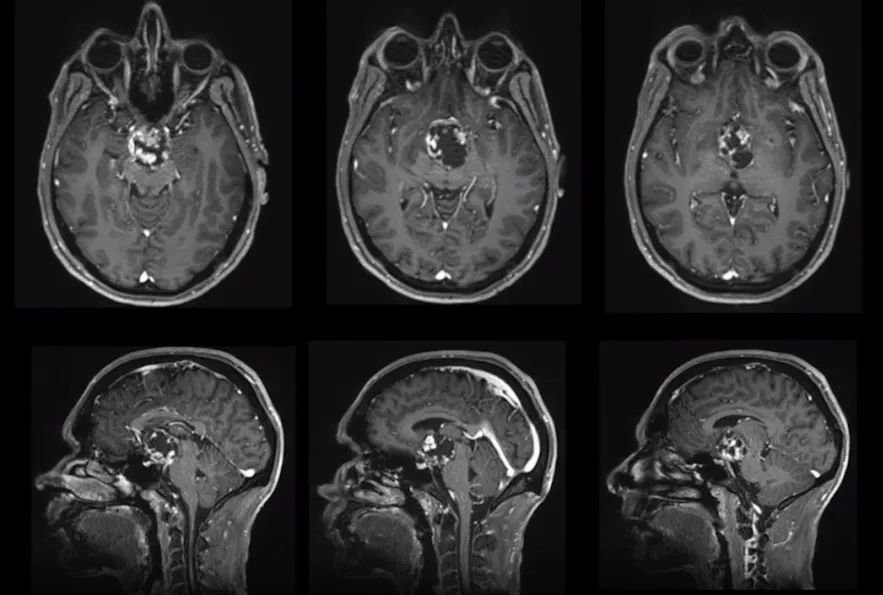

病史摘要:颅咽管瘤,已经压迫三脑室及视神经,导致步态紊乱和认知障碍,视野缺损,全垂体功能减退伴轻度高泌乳素血症。严重影响到正常的工作与生活,手术高难度、。

手术记录:福洛里希教授结合患者实际病情制定了个性化的手术切除方案,保障肿瘤全切并较大水平保护了神经功能。

一阶段,通过经神经内镜经鼻入路进行视交叉和神经减压,从而为后续治疗做准备。然而随着肿瘤的加速生长,新的视觉缺陷出现和对下丘脑和三脑室的压迫影响,需要再次手术切除。二阶段,经后岩骨入路(或称后迷路经天幕入路)可以很好地暴露肿瘤和周围解剖结构(三脑室的底部和壁,分支血管,视神经等)。

图1后视交叉性较大颅咽管瘤患者肿瘤术前(A,C)和术后(B,D)矢状位增强MR对比,显示肿瘤全切。

图2术中图像:(A)在经后岩骨入路时,横窦-乙状窦连接处的后部移位,为颞叶与后颅窝之间的手术通道(白色箭头)。(B)脚间池蛛网膜的初步解剖分离,肿瘤的暴露。内窥镜辅助可以对手术床进行详细检查(C),以便更好地了解周围的神经血管解剖结构(D)。CN,颅神经;L视神经N,左视神经;R视神经N,右视神经。

术后情况:术后威尔视力、视野恢复正常,没有颅神经麻痹症状,认知功能好转,垂体功能恢复正常。术后配合辅助放射治疗,术前症状得到很大好转,可以如常工作,生活质量得到很大改观。